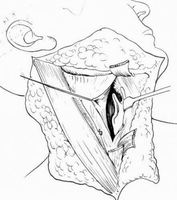

BPTM - Mandibulární split

Mandibulotomie

- Mediální

- Paramediální

- (Para)laterální

Kost nepostižená tumorem